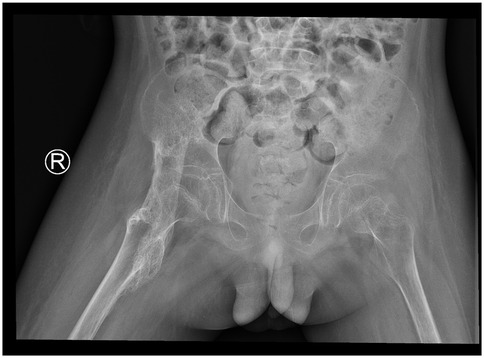

During rehabilitation in September 2020, significant restriction of right hip motion was noted. Pelvic x-ray revealed a high-density ossified mass along the course of the right iliopsoas muscle, with blurred margins and extension across the hip joint (Figure 1). As the ossification was presumed to be in the early to intermediate stage and not yet fully matured, conservative management including adjustment of rehabilitation exercises to avoid excessive mechanical stress, and close radiographic follow-up was recommended. Pelvic x-rays were obtained every 4–6 weeks to monitor lesion progression, with assessment of density, margin definition, and trabecular development to determine the appropriate timing for surgical resection.

Figure 1

X-ray image of the pelvis and lower abdomen showing the bones, including the pelvis and upper femurs. A marked \

Figure 1. 2020.09. A high-density ossification with blurred edges and cross-joint growth can be seen in the iliopsoas muscle area of the right hip, indicating that it is not yet fully mature.